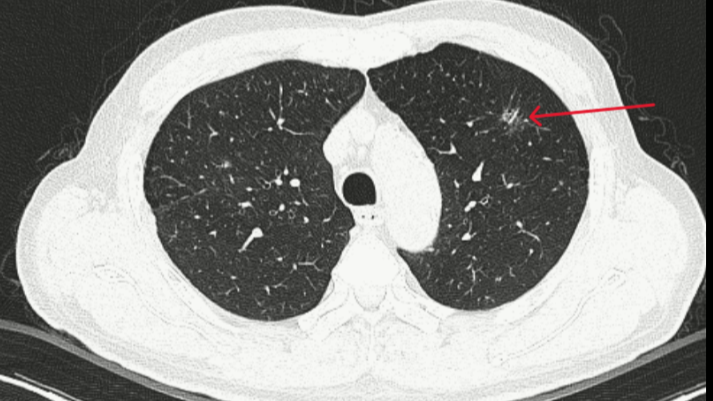

Điều đáng nói là trong quá trình chụp CT để đánh giá tổn thương thận, hình ảnh lại vô tình để lộ một tổn thương dạng kính mờ, có bờ tua gai ở thùy trên phổi trái – một dấu hiệu gợi ý tổn thương ác tính. Bệnh nhân có tiền sử tăng huyết áp, từng bị tai biến mạch máu não (không di chứng) và thói quen hút thuốc lá khoảng 20 bao/năm.

Ngay lập tức, bệnh nhân được chuyển đến Trung tâm Y học hạt nhân và Ung bướu để đánh giá sâu hơn. Tại đây, điểm đặc biệt nhất là tổn thương phổi trên phim CT đã được đưa vào hệ thống AI để phân tích. Kết quả, AI đưa ra xác suất tổn thương này là ác tính lên đến 97%.

Kết quả giải phẫu bệnh sau mổ đã xác nhận chẩn đoán: ung thư biểu mô tuyến giai đoạn pT1aN0M0 (giai đoạn IA). Đây là giai đoạn rất sớm của ung thư phổi không tế bào nhỏ, với tiên lượng điều trị cực kỳ khả quan. Đáng chú ý, mô bệnh còn phát hiện tình trạng viêm lao kèm theo. Bệnh nhân không có đột biến gene EGFR hay ALK.